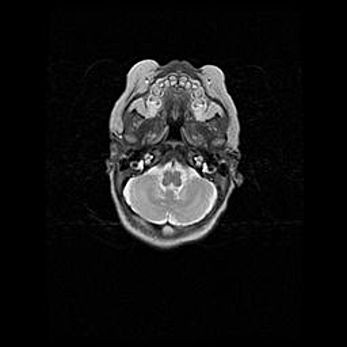

Мальформация Денди-Уокера. Киста задней черепной ямки.

Агенезия мозолистого тела.

Возраст: 2,5 месяца

Вес: 2420 г

Пол: женский

Окружность головы: 37 см

Срок гестации: 32 недели

Мальформация Денди—Уокера — редкий вид патологии ЦНС, представляющий собой врожденный порок развития каудального отдела ствола и червя мозжечка, ведущий к неполному раскрытию срединной (Мажанди) и латеральных (Лушка) апертур IV желудочка мозга. Для этогно синдрома характерна триада симптомов: гипотрофия червя мозжечка и/или полушарий мозжечка, кисты задней черепной ямки, гидроцефалия различной степени. В 70% случаев порок сочетается и с другими аномалиями головного мозга, в частности с агенезией мозолистого тела.